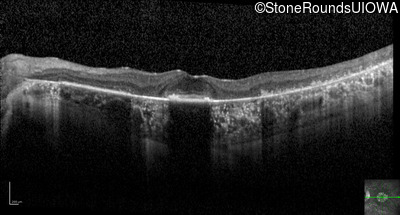

Optical Coherence Tomography - Left - 20/32

Exemplar / OCT Stack